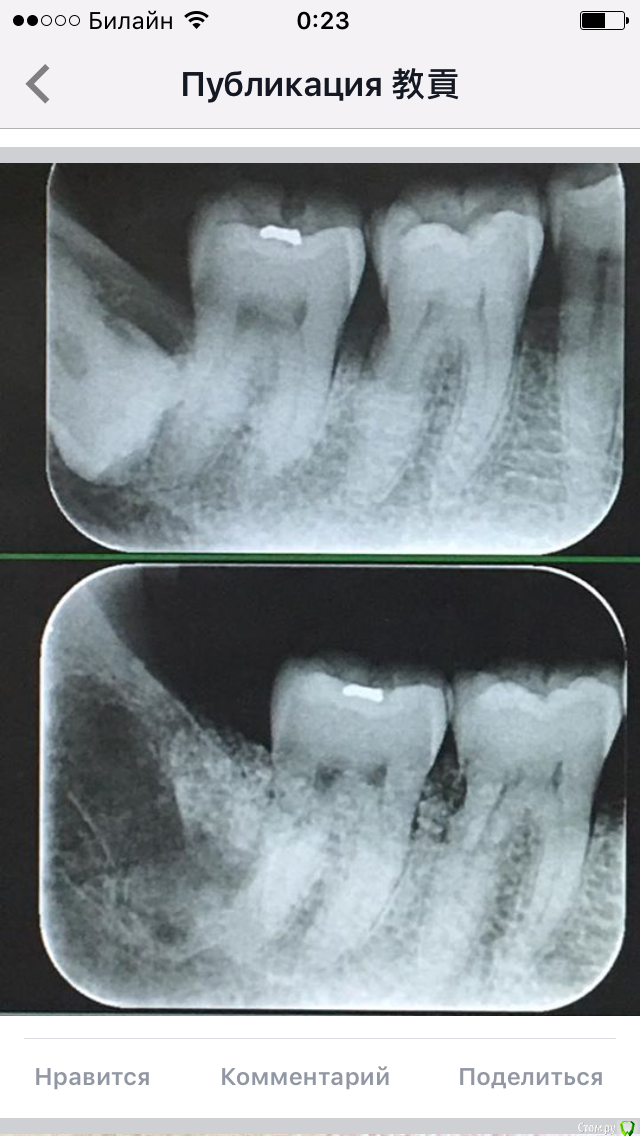

колесников Опубликовано 2 апреля, 2017 Автор Поделиться Опубликовано 2 апреля, 2017 Тройной лоскут , вид через 5 -7дней. Снимок "до". И благодарность за скорое заживление 6 Ссылка на комментарий

колесников Опубликовано 8 апреля, 2017 Автор Поделиться Опубликовано 8 апреля, 2017 Из публикации группы PIISC на фб. И да,это графт в лунке Ссылка на комментарий